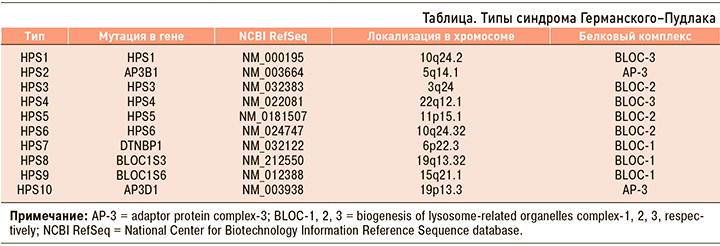

В настоящий момент описано 10 типов HPS в зависимости от локализации мутации и клинических проявлений. HPS1 и HPS4 имеют наиболее тяжелые проявления (табл.). HPS1, HPS2 и HPS4 ассоциируются с легочным фиброзом. Пациенты с HPS3, HPS5, HPS6 имеют менее выраженные симптомы.

Компьютерная томография (КТ) с высоким разрешением – предпочтительный метод визуализации при оценке выраженности заболевания легких у пациентов с синдромом Германского–Пудлака, поскольку рентгенограммы грудной клетки не позволяют объективно оценить объем и характер поражения легких. Рентгенологические паттерны ранней стадии заболевания сходны с идиопатическим легочным фиброзом и включают утолщение перегородок, феномен «матового стекла» и легкую ретикуляцию. На более поздних стадиях заболевания отмечаются тяжелые ретикулярные изменения, бронхоэктазы, субплевральные кисты и перибронхиально-сосудистое утолщение. Изменения на компьютерной томограмме высокого разрешения отмечаются в средненижних отделах с тенденцией к периферии. Тем не менее по мере прогрессирования заболевания в процесс вовлекаются все легочные поля [5].